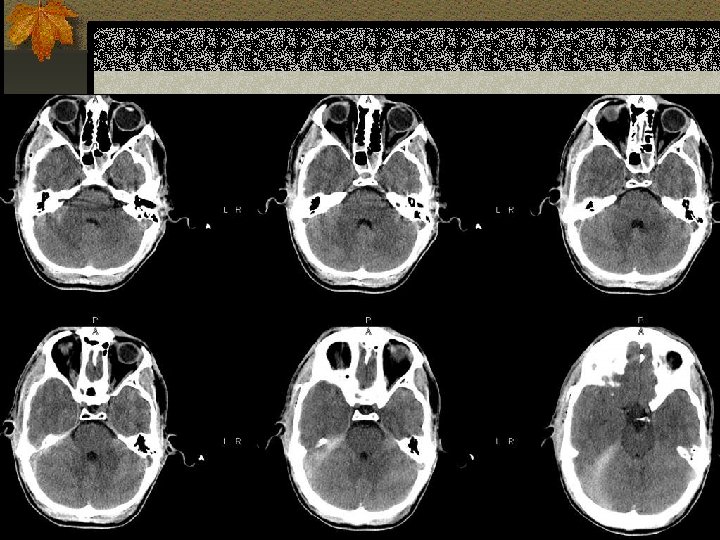

EPIDURAL HEMATOMA n Berlokasi antara skull dan periosteum n Akibat laserasi arteri meningea media atau vena dural n Dibatasi oleh sutura n Bentuk lentiform / bikonveks

PENANGANAN EDH n EDH > 30 cm 3 harus dievakuasi n EDH < 30 cm 3 dan ketebalan <15 mm dan pergeseran midline < 5 mm dan GCS >8 dapat diobservasi dengan serial CT

Perdarahan Intraventricular n Paling sering akibat ruptur pembuluh darah subependymal n Dapat timbul akibat refluks dari SAH atau perluasan dari perdarahan intraserebral n Lihat adanya blood-cerebrospinal fluid level di occipital horns